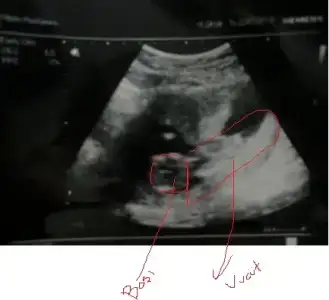

dr soylemeden siz gorun genital nub teorisi ( bebegin cinsiyeti)

Şimdi biz 14 hafta 2 günlüyüz.Eşimle oturub baktık iyice.Belki ben yalnış görürüm diye söyledim o baksın)))beyaz bişey var yukarda.O mu çıkıntı acaba?

Evet cnm ayni seyi goruyoruz ilk sayfadakilerle kiyasla istersen

Ama parlayan degil onun altinda daha kucuk bir cikinti var

parlayan kemigi olsa gerek

doğru mu işaretledim,bakarmısın canım?Yordum da seni bugün,kusura bakma canım)